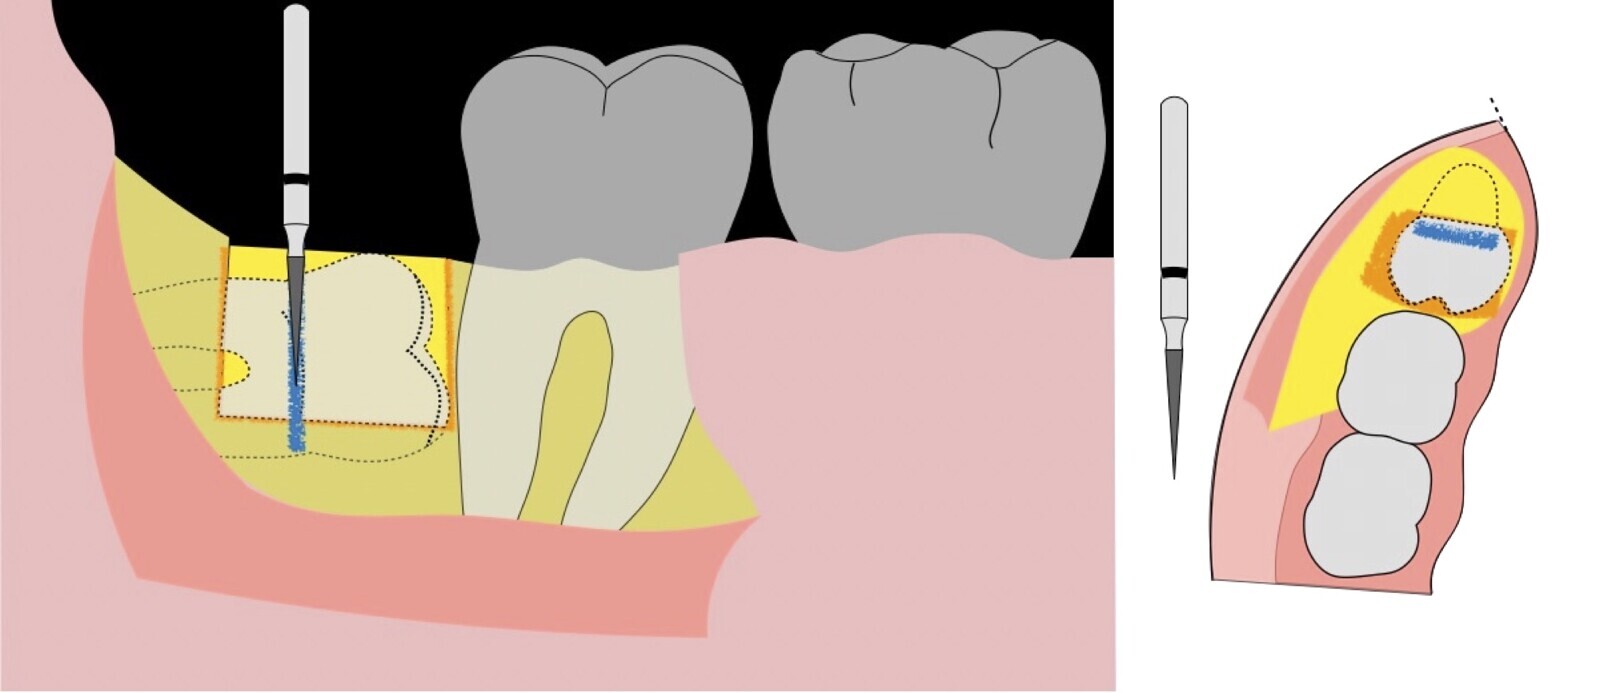

Figura 8. Odontosección mediante fresa de alta rotación y/o inserto de corte de piezoeléctrico. Posteriormente se procede al ensanchamiento del espacio pericoronario con el periótomo de piezoeléctrico para facilitar la avulsión de la pieza dentaria.

Figura 9. Avulsión de la parte coronaria de la tercera molar.

Figura 10. Tracción mesial del remanente dentario utilizando botadores en bandera.